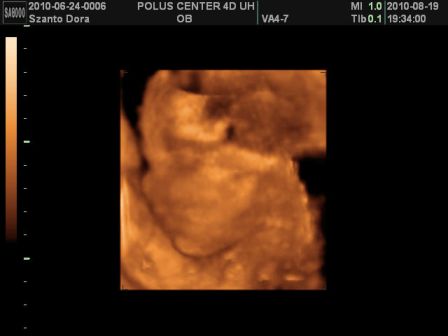

Basszus! Hívtam a kórházat, kiderült a dokim szabin, csak jövő héten szerdán lesz, de menjek be mindenképpen az ügyeleteshez! Na, anyuval felkerekedtünk és irány a kórház. Először csináltak egy uh-t! Dani épp fent volt és akkorákat rúgdalt, h patogott a nőci kezében a vizsgáló kütyü!

Megint nagyobbra mérték egy héttel, szóval továbbra is tartjuk a november elejét, mint születés. És farfekvéses a drágám egyelőre...

Viszont, most már 1360g volt a súlya az 1 héttel ezelőtti 1160g-hoz képest!